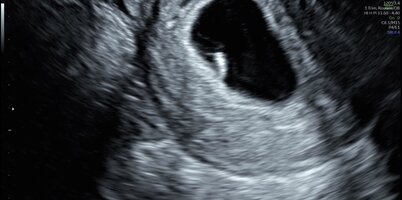

Kävin eilen yksityisellä, kun tämä jäi tosiaan mietityttämään kovasti. Ultrassa näkyi 8+4 vastaava alkio sykkeellä ja liikahti kertaalleen myös muuten 😍 Helpotti oloa ihan mielettömästi! Kätilö pyysi myös näyttämään alkuperäisen ultrakuvan ja hän oli hyvin ihmeissään siitä, miksi sellainen kuva on edes annettu minulle mukaan. Sanoi, että kyseisessä kuvassa ei näy kuin jotain kalvoa. Tuli siitäkin ihan hyvä fiilis, etten selkeästi ollut ”ylireagoinut” huonon ultrakokemuksen takia. Onneksi kaikki näytti olevan hyvin ❤️